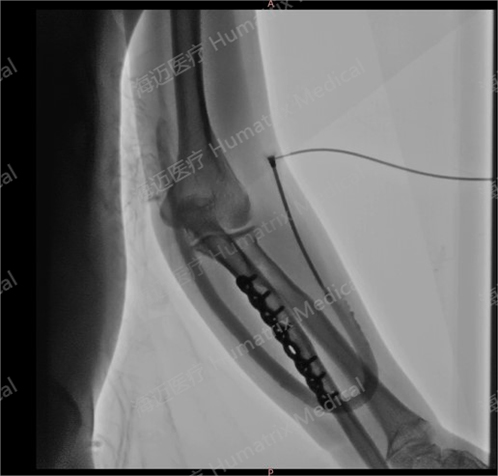

臨床隨訪結果顯示,產品完成植入后,患者術后3月初級通暢率90.9%,累積通暢率100%;術后6月初級通暢率80.8%,累積通暢率100%。人工血管未引發人體免疫反應,無感染及動脈瘤等并發癥發生,產品性能明顯優于ePTFE人工血管,臨床效果優異。

臨床試驗患者使用LineMatrix耐邁通?生物型人工血管長期血液透析,血管造影通暢。

此次臨床試驗由浙江大學醫學院附屬邵逸夫醫院腎內科與血液透析中心主任李華擔任主要研究者。產品于2024年9月24日首例植入,并于2025年6月5日完成所有入組患者臨床隨訪。在李華看來,LineMatrix耐邁通?生物型人工血管用于建立終末期腎臟病患者移植物動靜脈內瘺臨床效果優異。所有患者均使用植入人工血管進行血液透析,初步證實LineMatrix耐邁通?生物型人工血管在人體內的安全性和有效性。“傳統ePTFE人工血管6月初級通暢率最高不超過50-60%。LineMatrix耐邁通?生物型人工血管通暢率高,使用后可顯著減少患者術后干預次數,節省醫保資金并極大減輕患者經濟負擔,為血管通路建立提供國產新方案,有望逐步替代傳統ePTFE人工血管,惠及廣大患者。”